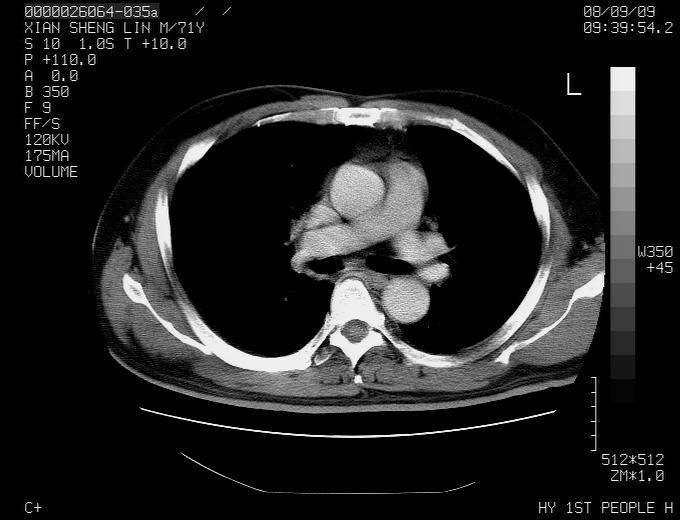

标题: CT15869:男性,71岁,因咳嗽而就诊,请讨论右上肺病变性质 [打印本页]

标题: CT15869:男性,71岁,因咳嗽而就诊,请讨论右上肺病变性质

患者,男性,71岁,因咳嗽而就诊,

典型的右肺中心性肺癌并纵隔淋巴结转移

右肺中心性肺癌并纵隔淋巴结转移可能性大!

右肺中心性肺癌并纵隔淋巴结转移可能性大! 支持!

病灶中等程度强化 还是支持肺癌诊断

考虑右肺中心性肺癌并右肺门及纵隔淋巴结转移。

1,右肺中心型ca,气管隆突旁淋巴结转移。